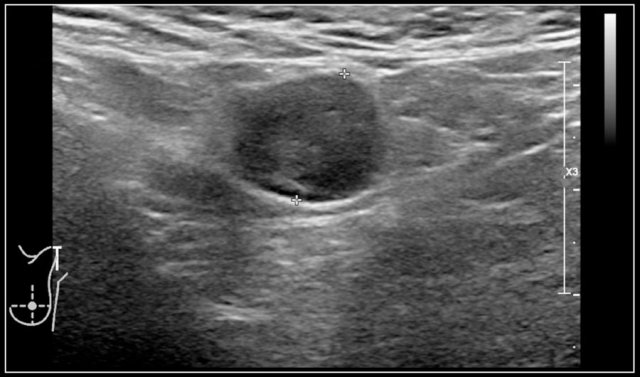

Here an ultrasund image of a sixteen-year-old girl, who was treated for recurrence of acute lymphatic leukaemia.

Six months after the last treatment, she developed a swelling in the left shoulder region.

A hypoechoic node without any internal structure was seen.

It was excised.

The final diagnosis was, surprisingly, Bartonella henselae.